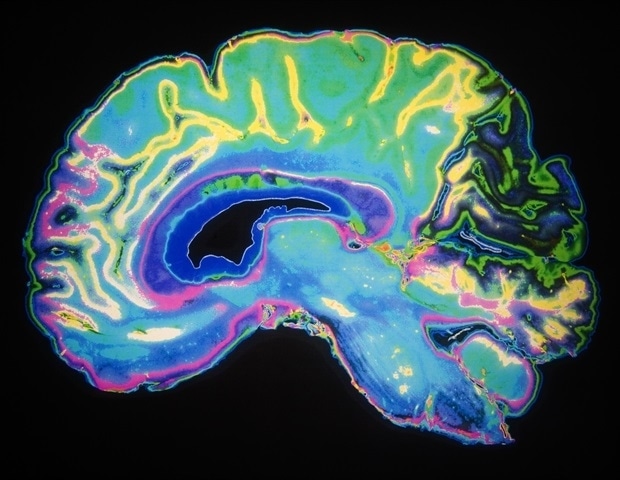

Alzheimer’s disease disrupts patients’ daily rhythms significantly, manifesting as restless nights and increased daytime napping. These early signs, along with confusion during the evening hours, indicate an intricate relationship between the disease and the circadian system, which governs sleep and wake cycles. Researchers at Washington University School of Medicine in St. Louis have uncovered that circadian rhythms within specific brain cells are disrupted in Alzheimer’s disease, influencing the regulation of hundreds of genes essential to brain function. The findings, published on October 23, 2025, in Nature Neuroscience, suggest that targeting these disrupted rhythms could offer new therapeutic avenues for treatment.

The research revealed that amyloid accumulations disrupt the daily rhythms of numerous genes in brain cells, specifically microglia and astrocytes. Microglia are crucial for the brain’s immune response, while astrocytes support neuronal communication. Although the circadian disruption did not completely shut down the affected genes, it transformed a coordinated sequence of activities into a chaotic pattern, potentially hindering the brain’s ability to clear amyloid effectively.